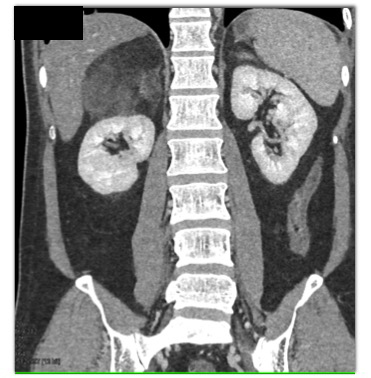

The best diagnosis in this case is?

Adrenal myelolipoma

Adrenal sarcoma

retroperitoneal liposarcoma

Adrenal carcinoma